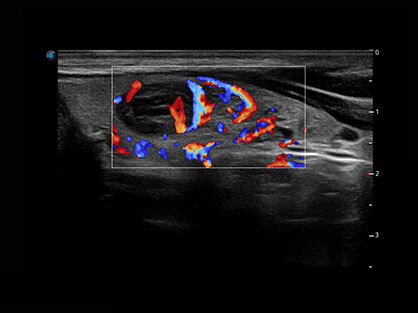

• Wi-Flow

通过对组织运动信息、血流信号及背景噪声进行准确智能的阈值判定,高效提取出微弱血流信号,获得高灵敏度和空间分辨率的血流图像,为临床提供更加真实和丰富的诊断信息。